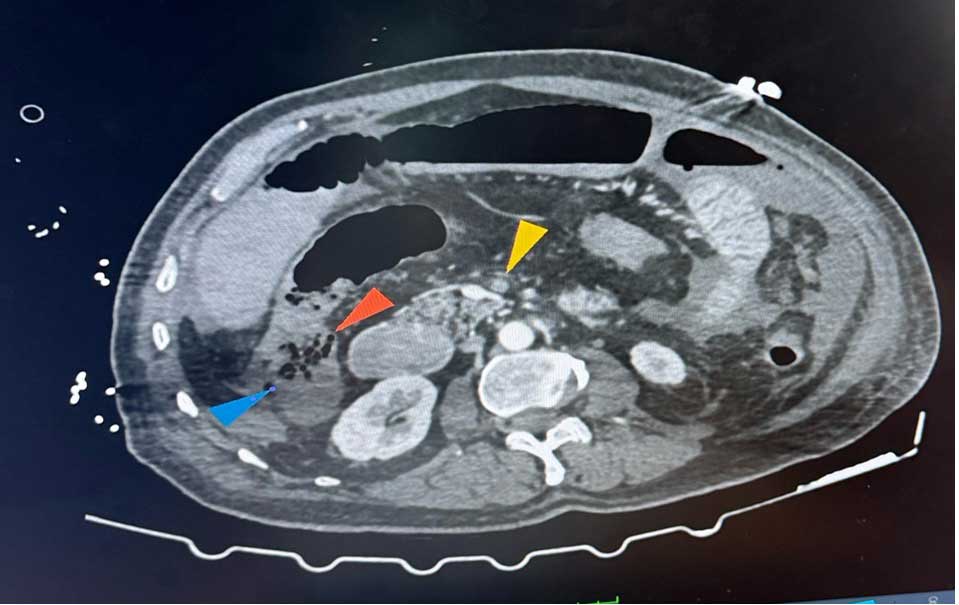

Annotated CT scan — used in planning colorectal surgery